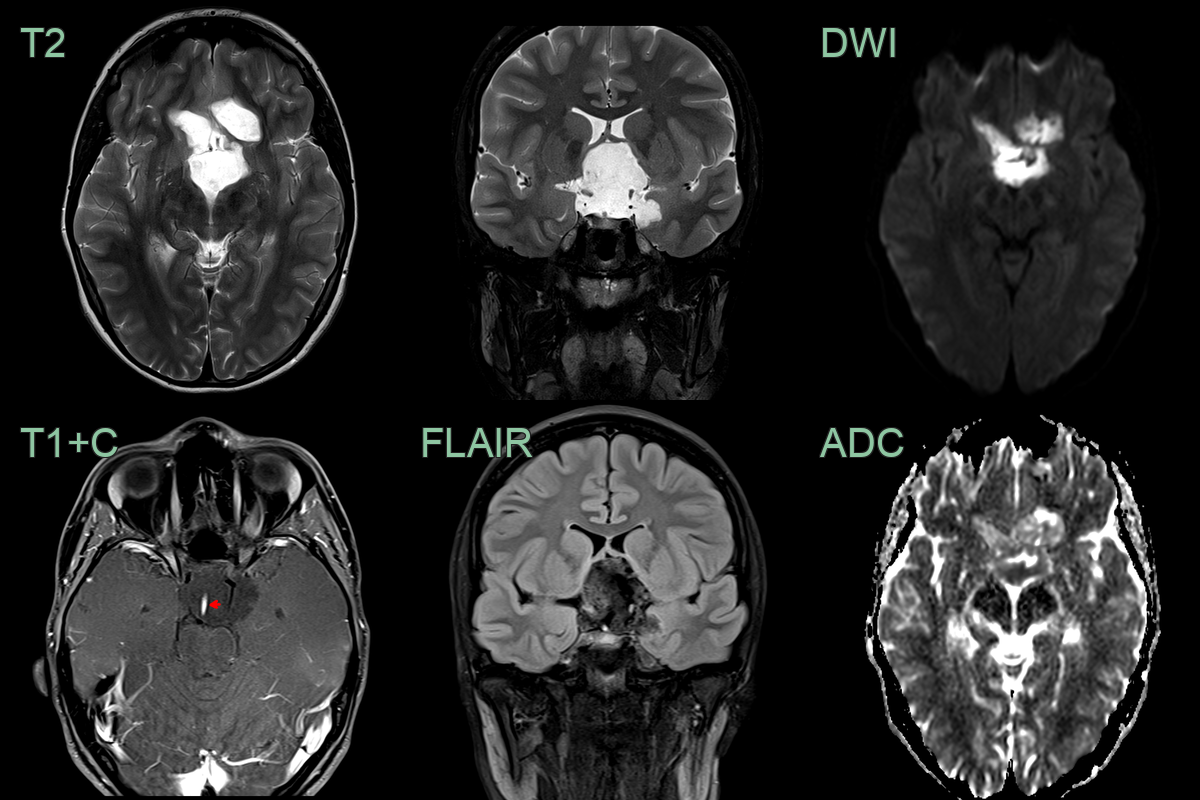

- MRI:

- T1: Hypointense to isointense

- T2: Hyperintense

- FLAIR: Heterogeneous signal intensity

- DWI: Marked restriction (key diagnostic feature)

- No enhancement with gadolinium

- "Popcorn" appearance on DWI due to lamellated keratin

- 60-year-old patient present with ataxia and poor left-sided hearing.

- MRI showed a T2-hyperintense non-enhancing lobulated lesion with low ADC values in the left side of the posterior fossa, encasing the 7th and 8th nerve complexes.

- There was significant mass effect on the cerebellum (presumably relevant to the ataxia) but there was no oedema, indicating that this lesion has grown slowly.